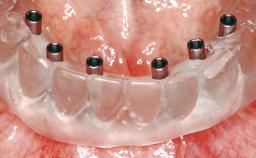

Immediate Loading of Eight Implants in the Maxilla and Six Implants in the Mandible and Final Restoration with Three-Unit and Four-Unit FDPs

Extensive scientific evidence has confirmed that immediately loaded implants with fixed full-arch provisional restorations can osseointegrate with success rates similar to conventionally or delayed loaded implants. A number of immediate-provisionalization techniques for edentulous jaws have been described. Some protocols differ when it comes to prefabricated provisional templates versus complete denture conversion; intrasurgical impressions versus direct relining; and cemented versus screw-retained provisional restorations. In this context, complete-denture conversion has been proposed for either intrasurgical impressions or direct relining. Another possibility is the utilization of a prefabricated provisional to be adapted either in the mouth (by direct relining) or in the laboratory (on a working model obtained from an intrasurgical impression).

# of Implants 14

Type of Implants One-Piece

Modality 6+ implants with immediate loading